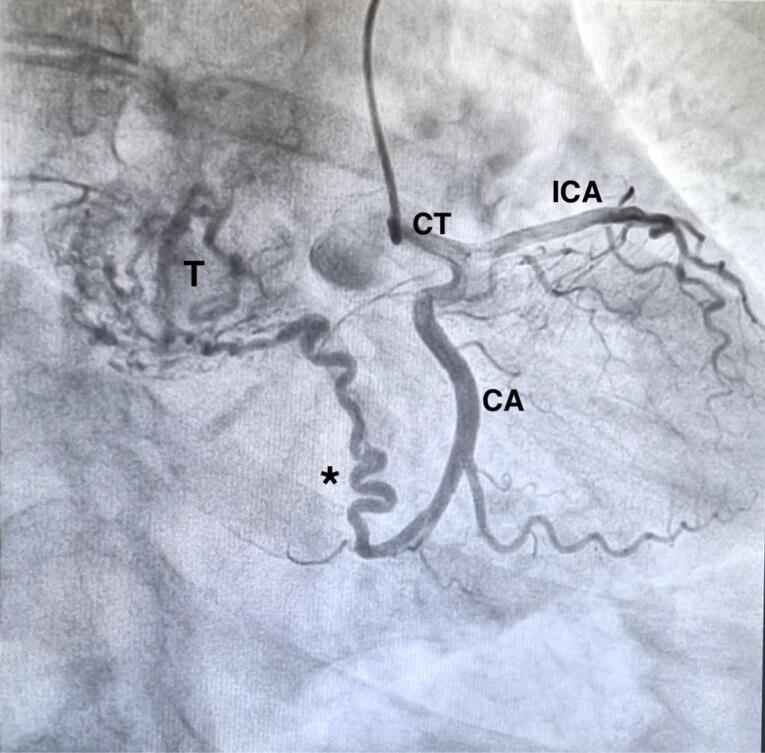

无功能性中纵隔副神经节瘤是一种罕见病。我们描述了一例 67 岁女性的病例,她在胸部 CT 和 18F 氟脱氧葡萄糖正电子发射断层扫描后,通过支气管内超声经支气管针吸术确诊为大纵隔副神经节瘤。肿瘤长约 9 厘米,位于上腔静脉和升主动脉后部之间,压迫左心房、气管和左主支气管,后方环绕右肺动脉。单孔右侧视频胸腔镜活检未得出结论,并发严重出血,但已得到控制。手术通过经胸腔经心包入路进行,然后进行心肺旁路和升主动脉切除,这样可以很好地暴露并更好地控制大血管和心脏。除左侧声带麻痹外,肿瘤完全切除,无围手术期并发症。12 个月后,患者已无疾病,全身状况良好。

A non-functional middle mediastinal paraganglioma is a rare entity. We describe a case of a 67-year-old woman with a diagnosis of a big mediastinal paraganglioma by endobronchial ultrasound transbronchial needle aspiration after chest CT and 18F-fluorodeoxyglucose positron-emission tomography. The nine centimeter in length tumor was located between the superior vena cava and the posterior portion of the ascending aorta, compressing the left atrium and the trachea and main left bronchus, posteriorly, surrounding the right pulmonary artery. Uniportal right video-thoracoscopic biopsy was unconclusive and complicated by severe hemorrhage, however controlled. Surgical resection was performed via a trans-sternal trans-pericardial approach followed by cardiopulmonary bypass and ascending aorta resection which allows an excellent exposure and greater control of great vessels and heart. Complete resection of the tumor was achieved without perioperative complication except for the left vocal cord palsy. Twelve months late the patient is disease free and in good general conditions.